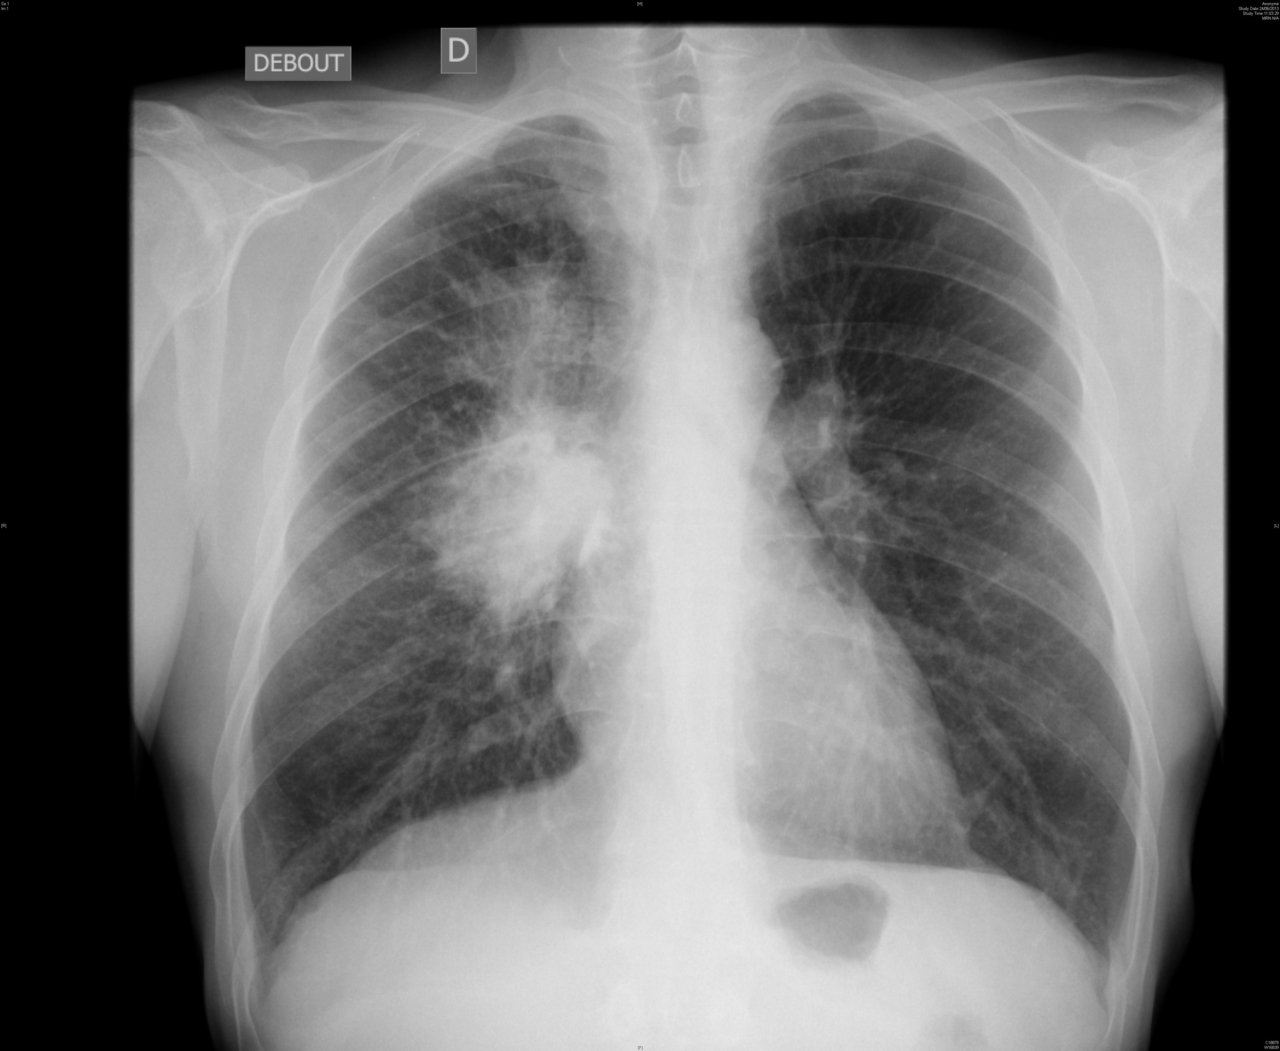

Le patient est perdu de vue. Trois ans après le passage en réanimation, il est revu pour une altération de l’état général par son médecin traitant qui lui prescrit une radiographie de thorax standard dont voici l’image.

Figure 6.

Le médecin traitant suspecte une lésion maligne bronchopulmonaire droite et l’adresse donc au pneumologue pour une documentation histologique de cette masse.

Lésion proximale péri-hilaire.

La documentation d’une lésion thoracique dépend de sa localisation. Les lésions proximales péri-bronchiques sont à explorer en première intention par endoscopie bronchique simple. Les lésions périphériques sous-pleurales sont accessibles par ponction transpariétale écho- ou scanno-guidée en première intention, sinon par chirurgie (vidéo-thoracoscopie). Entre les deux, l’endoscopie bronchique simple est à tenter en première intention, la ponction transpariétale écho- ou scanno-guidée en deuxième intention, et la chirurgie en troisième intention. Les ganglions médiastinaux sont biopsiables par écho-endoscopie bronchique (EBUS, pour endobronchial ultrasound) ou médiastinoscopie. Pour l’EBUS, le ganglion doit absolument être au contact de l’arbre bronchique pour être visualisé et biopsié.